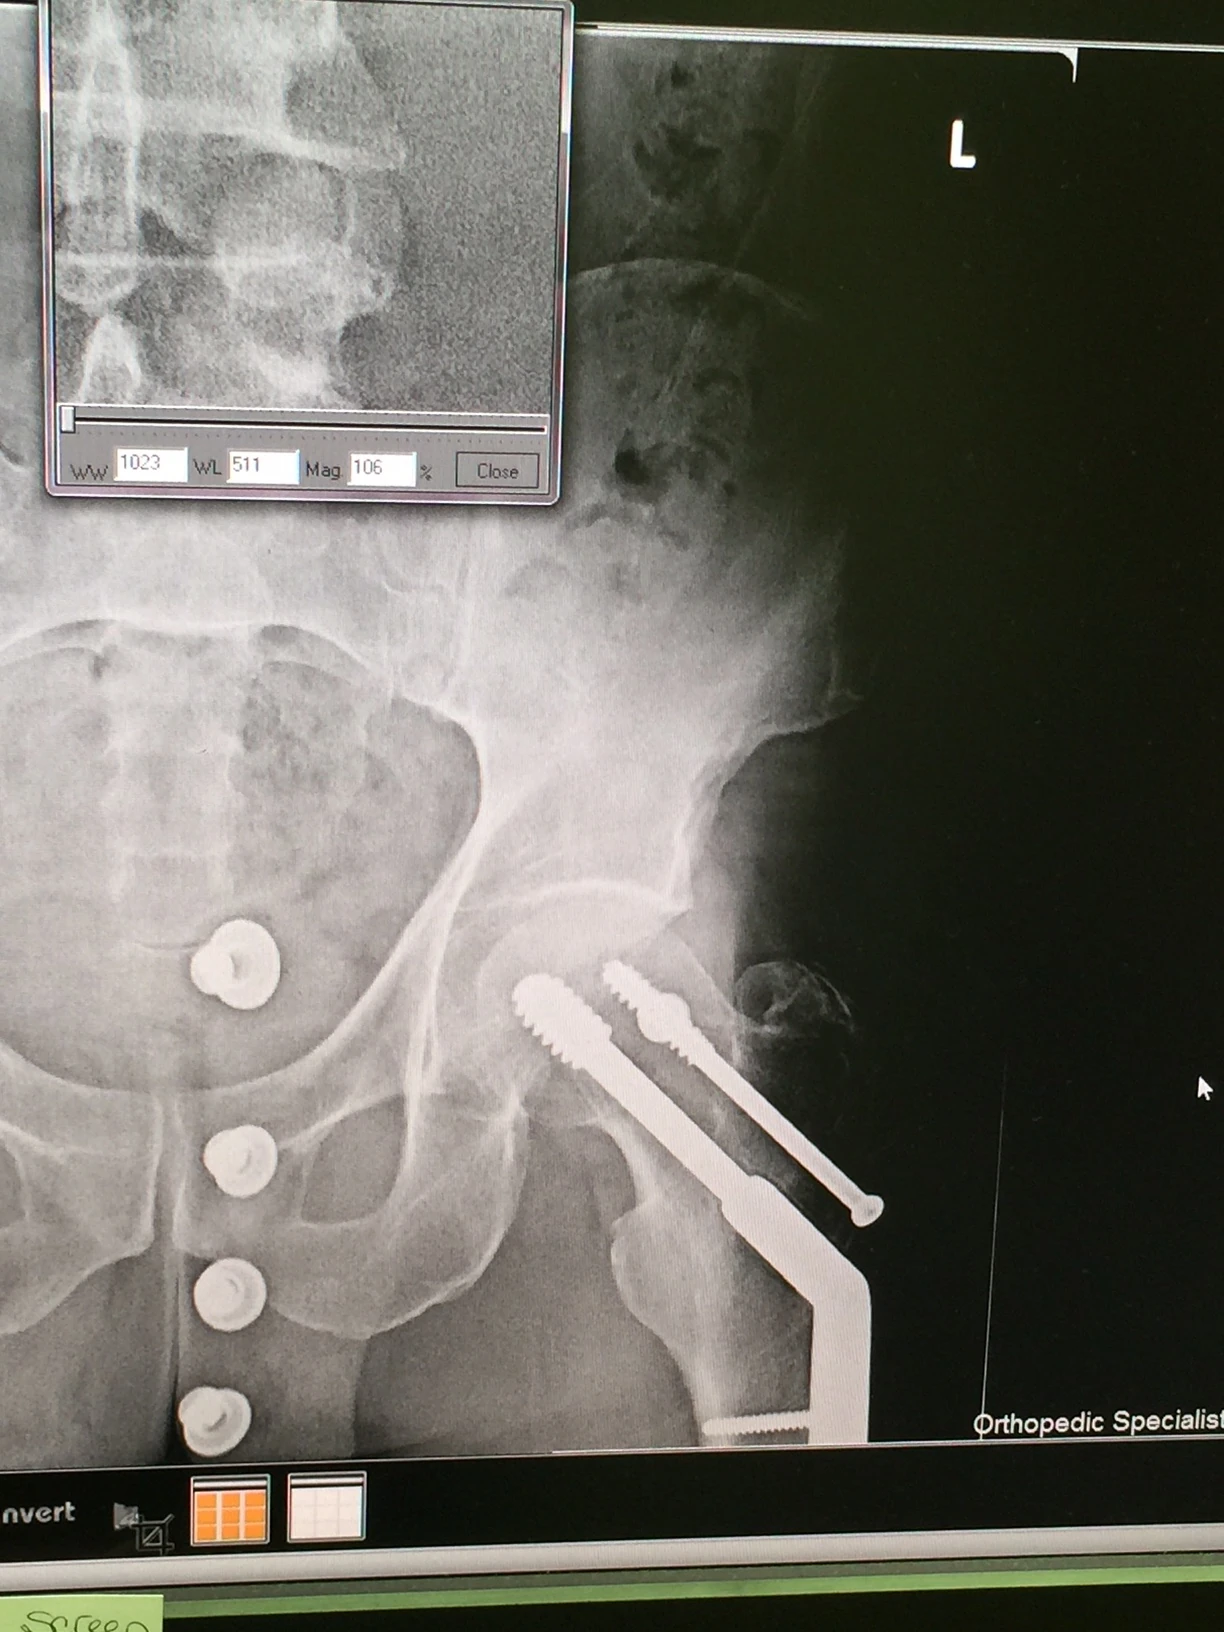

Last night my friend Stacie organized a Pro party for youth cyclocross here in Louisville. It is amazing the schedule that woman keeps. I had a little glimpse of some of her day yesterday and it was crazy. I went to her office mid day to get a x-ray of my thumb. Her office was a zoo. An organized zoo, crazy busy, but manageable, I guess. Turns out my thumb is broken. But, I knew that already. It still hurts pretty much, but nothing like it did 2 weeks ago. Plus, there is nothing that I have to do differently, so that is great. I came back to her house to get ready to ride. I was thinking I had all this time, but I didn’t realize that I hadn’t reset my watch from Chicago and it was off an hour. So all of a sudden 2:30 became 3:30. And the get together was starting at 6. I hurried and rode down the RIver Road over to the course. It had rained over an inch I hear, so expected it to be pretty soupy. At the bike wash, most of the bikes were pretty muddy, but not clogged up. But they were riding the whole course. I just rode the top section that serpentines up and down the hill. It was slick, but not muddy. I really didn’t put any effort into getting the lines down because it was going to be so much different today at 6. Anyway, I hightail it back to Prospect, which is 11 miles, and just get back in time to shower and get ready for the party. There were close to 100 people here. Lots of good food, wine, beer, etc. There were so many kids. And the U of Louisville cycling team had representation. There were a lot of really good riders that were on the panel for questions. Katie Compton, Ryan Trebon, Gage Hecht, Kaitlin Antonneau, Gavin Haley, Dan Timmerman, Jake Wells, Ally Stacher and a few others. It was super knowledgable group and there was a lot of information that was exchanged. Every race should have a meet and greet party like this. Today is going to be done in a blink. It is already late morning, I’m still on California time, and it is T-7 hours to race time. I’m going to suit up and do the 30 minute ride over to the course and do a couple laps between races. I have no illusions on how I’m going to do here. I very much doubt I’ll survive the 80% rule, which I think is bullshit. I haven’t seen the sandpit and am hoping it doesn’t jack up my drivetrain too much. Mike Crum left a comment yesterday about being unprepared for all the racing I’ve done. He is absolutely correct this time. I am super unprepared. I haven’t dismounted or mounted a cyclocross bike in two years and didn’t have enough time to get the correct equipment together for my liking. But I felt that I need to get back into the race scene and this was the first opportunity. I’ll be better in a month or so. The panel. The young guys had some great perspectives. The food was pretty impressive. Katie and I. Hip looks good. Buttons of my jeans are the dots. Broken thumb. Little hard to see the break in this picture, but it is pretty broke.